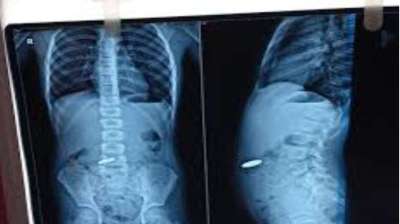

खेलते-खेलते बच्चे ने निगल लिए सिक्के, खाने की नली में फंसे; डॉक्टरों की टीम ने ऐसे बचाई जान

दिल्ली : दिल्ली के एक सरकारी अस्पताल के डॉक्टरों ने 12 वर्षीय बच्चे की जान बचाई है। बच्चे ने पांच और दस रुपये के तीन सिक्के निगल लिए थे। सिक्के...